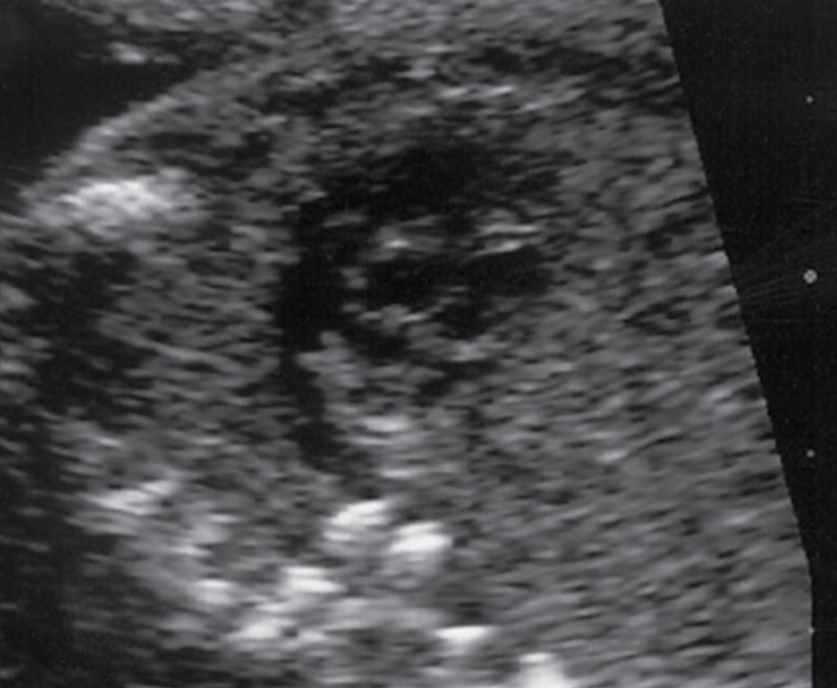

CDH